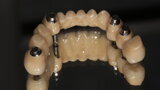

Fig. 12: Crowns on printed model.